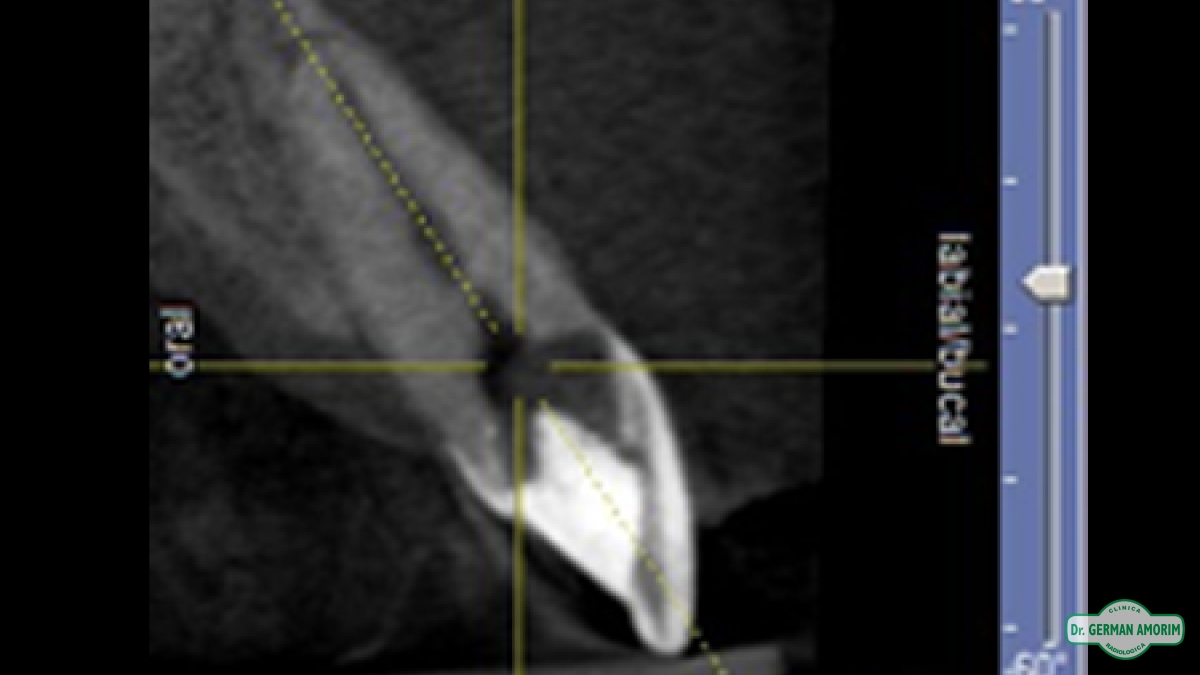

La radiografía tridimensional también tiene mucha utilidad de en Endodoncia como se ve en este caso que detallamos a continuación.

El profesional no podía encontrar el conducto en la radiografía periapical estándar. Al ser bidimensional no lo veía y por eso le indicó una tomografía volumétrica digital (TVD).

En la imagen tridimensional se pudo apreciar dónde estaba el conducto . Como se ve en las imágenes tridimensionales faltó muy poco para hacer una perforación ya que el profesional se estaba yendo hacia vestibular. Gracias a la TVD se pudo identificar y hacer el tratamiento de endodoncia sin problemas.